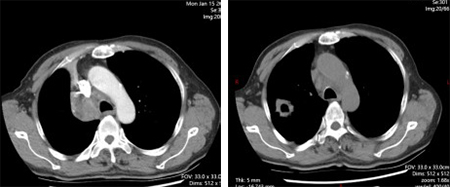

所谓的精准武器,就是当时国内新获批的可医保报销的高选择性MET抑制剂。1月12日,69岁的老李开始口服这种靶向药物——MET抑制剂。仅仅28天,咳嗽、痰血和喘憋就明显减轻。复查CT,原本被肿瘤压瘪的右上肺重新张开,连支气管镜下的“菜花”样新生物也缩小了近一半。老李高兴地说:“睡觉不再被憋醒,走路也能跟上儿子了。”

靶向治疗前;靶向治疗1个月后